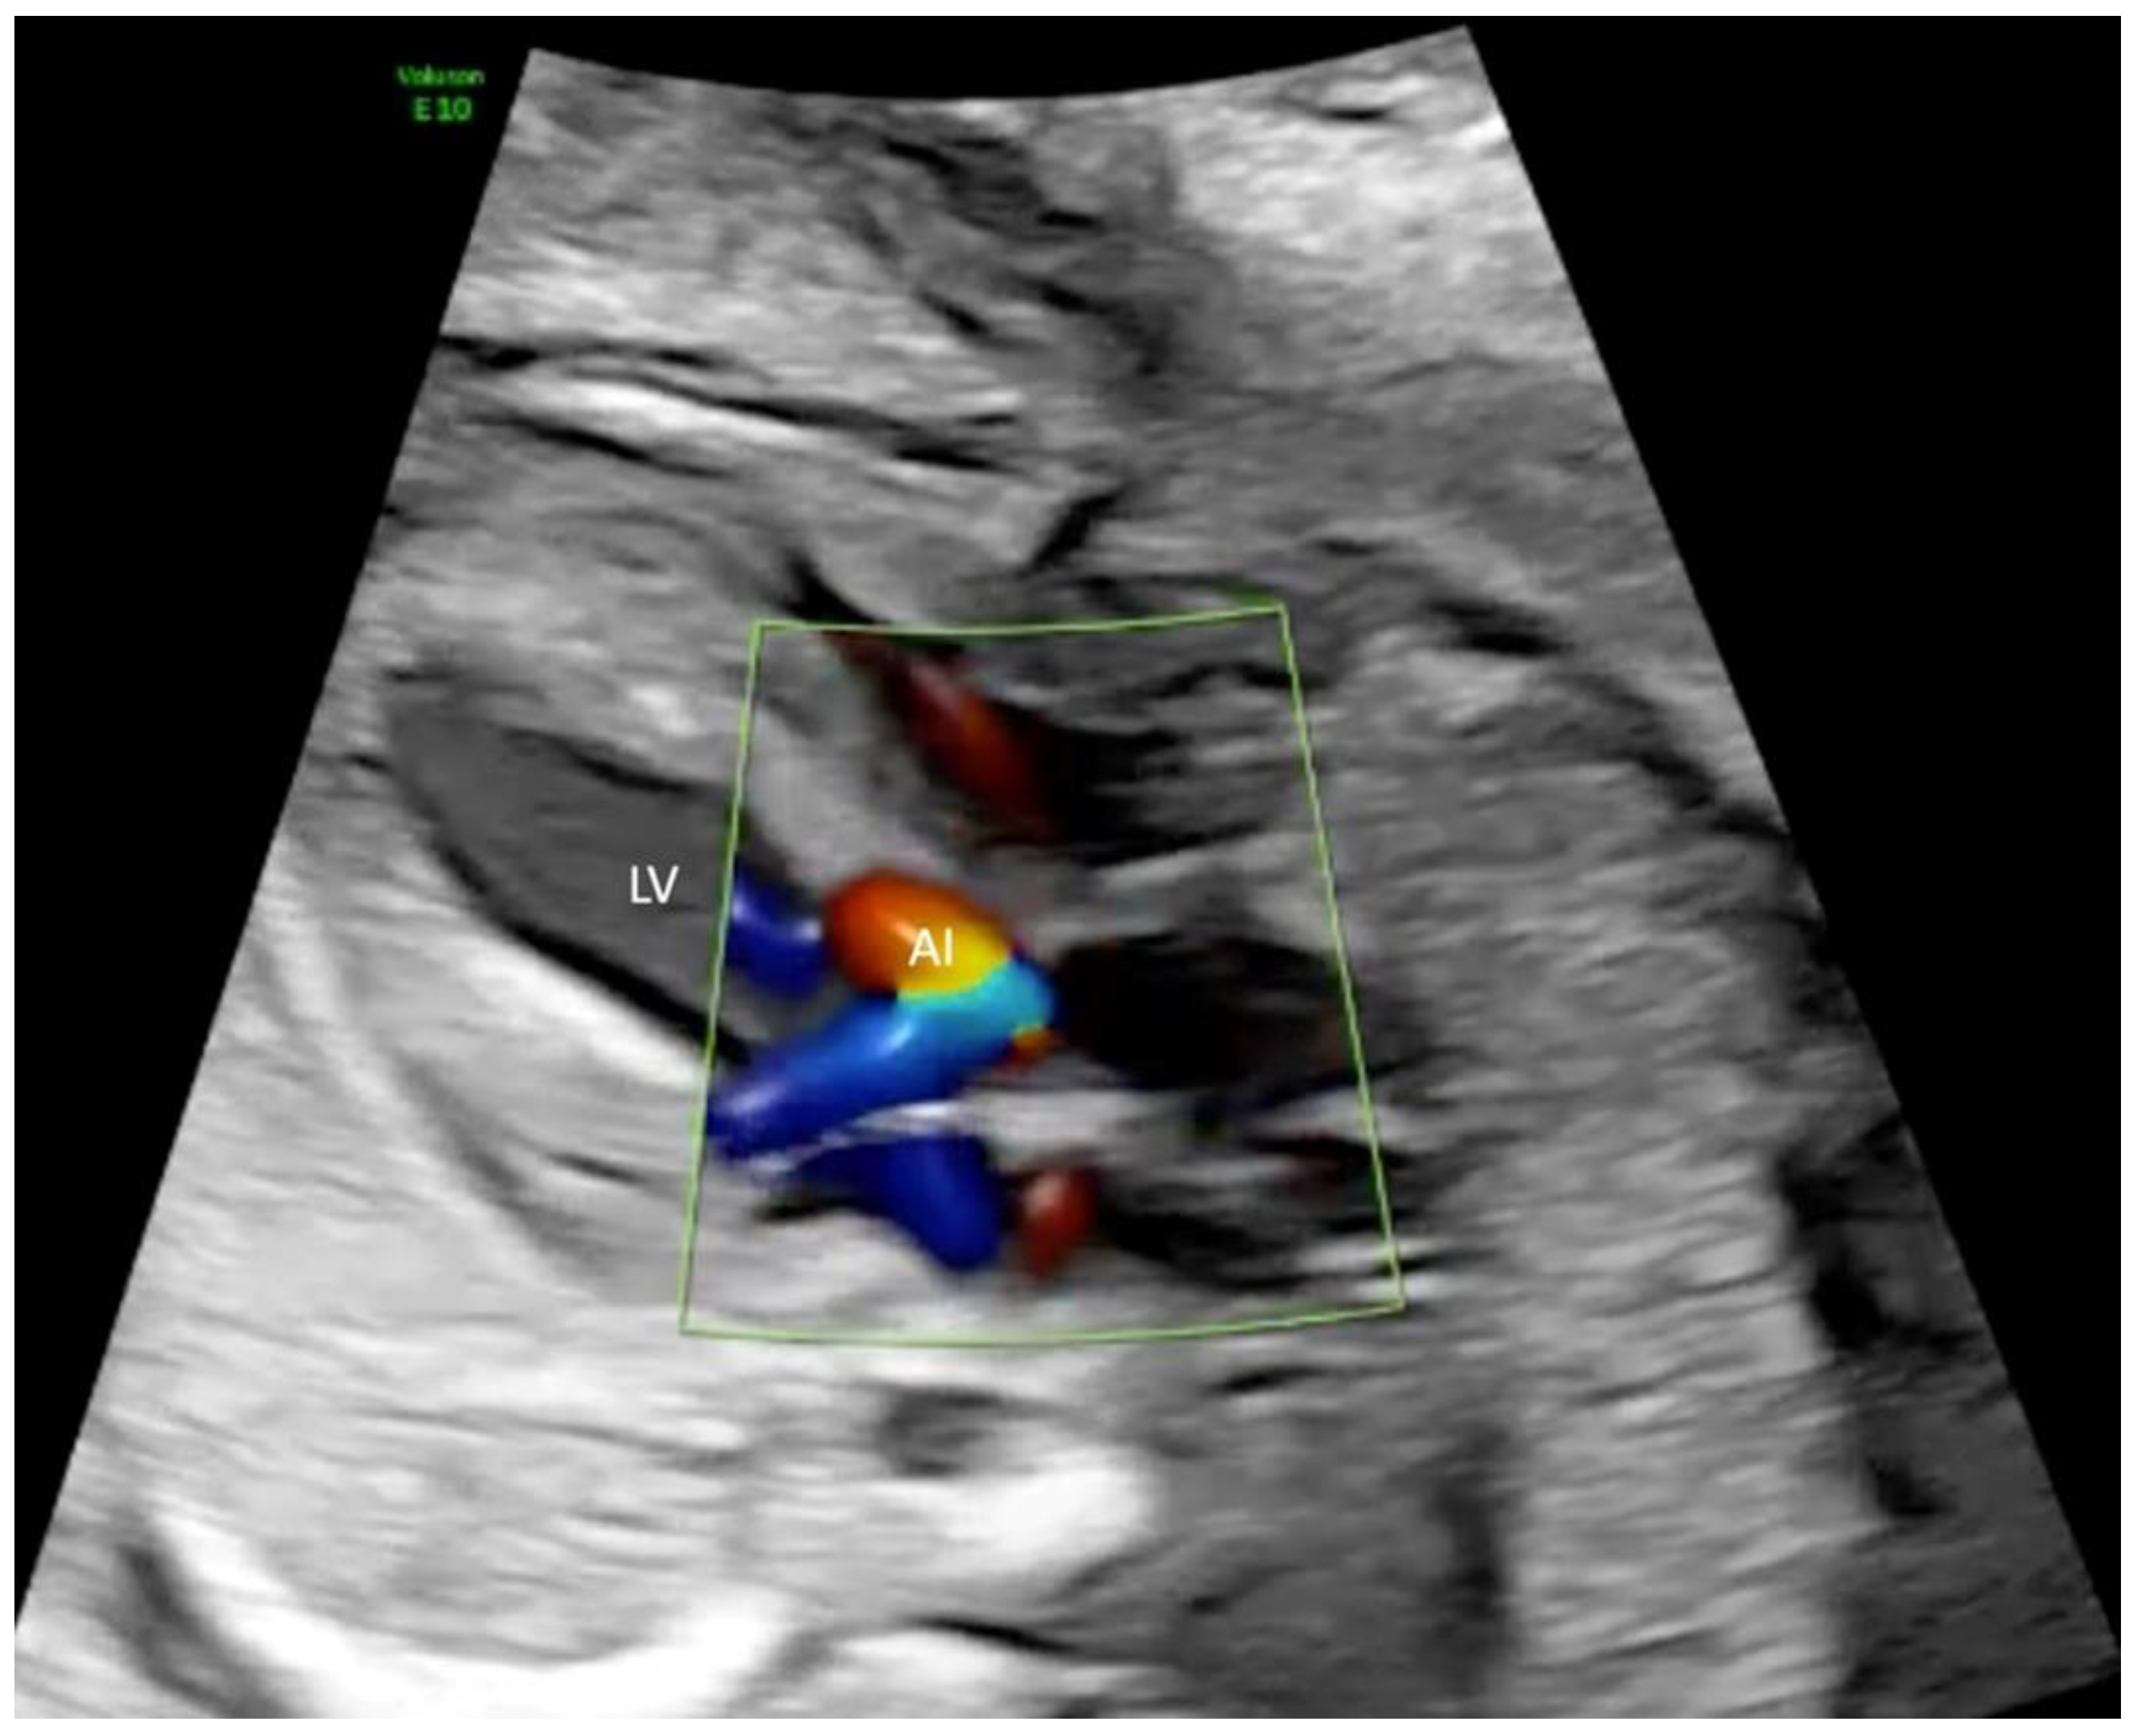

2.2. Procedure